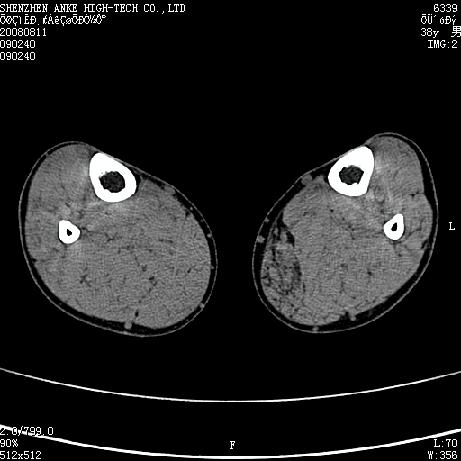

患者,男,38岁,右小腿疼痛性包块1月,查体:右小腿可扪及约5x4cm大小包块,压痛.

左小腿内侧软组织病变,性质待定(血管瘤?);建议行mri检查。